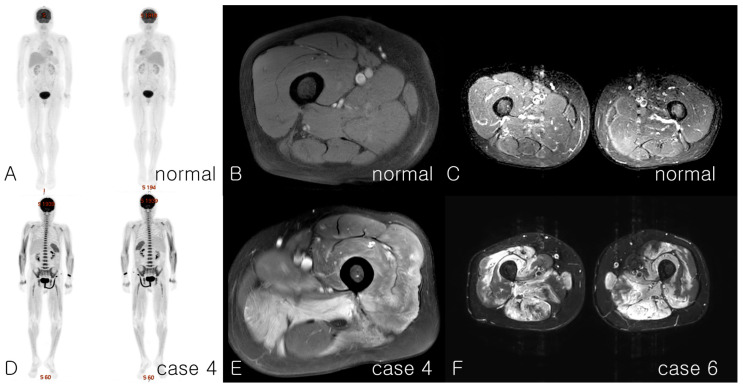

背景:免疫介导的坏死性肌病(IMNM)伴抗3-羟基-3-甲基戊二酰辅酶A还原酶(HMGCR)抗体是一种罕见但关键的并发症,通常由他汀类药物引起。然而,抗hmgcr阳性IMNM的综合表征和长期结果仍未得到充分探讨。本研究旨在探讨抗hmgcr阳性IMNM患者的临床特征、诊断挑战、治疗反应和长期预后。方法:回顾性分析2019年至2025年在单一机构诊断为抗hmgcr阳性IMNM患者的数据。通过检测抗hmgcr抗体并符合欧洲神经肌肉中心的IMNM标准,确诊。分析的数据包括人口统计学、临床表现、实验室结果、影像学结果、肌肉活检特征、治疗方案和随访结果。结果:纳入10例患者(6女4男),中位年龄58岁(33-86岁)。9例患者有他汀类药物使用史,平均持续时间为2年。平均诊断延迟时间为症状出现后233天。初始肌酸激酶(CK)水平在1438到13000 IU/L之间。肌肉活检显示肌纤维坏死和再生。CK水平在处理后180 d内波动并呈下降趋势。治疗包括皮质类固醇、甲氨蝶呤、硫唑嘌呤、他克莫司、霉酚酸酯、静脉注射免疫球蛋白和利妥昔单抗。从症状开始延迟治疗与延长治疗时间直到第一次缓解相关。结论:抗hmgcr阳性IMNM在症状出现后延迟治疗,预后较差。有必要进一步研究以确定不良预后标志物并开发相关治疗方法。

Background: Immune-mediated necrotizing myopathy (IMNM) associated with anti-3-hydroxy-3-methylglutaryl-coenzyme A reductase (HMGCR) antibody is a rare but critical complication usually triggered by statin use. However, the comprehensive characterization and long-term outcomes of anti-HMGCR-positive IMNM remain underexplored. This study aimed to examine the clinical characteristics, diagnostic challenges, treatment responses, and long-term outcomes of patients with anti-HMGCR-positive IMNM. Methods: A retrospective review was conducted at a single institution between 2019 and 2025 to analyze the data of patients diagnosed with anti-HMGCR-positive IMNM. Diagnoses were confirmed by detecting anti-HMGCR antibodies and meeting the criteria for IMNM of the European Neuromuscular Center. The analyzed data included demographics, clinical presentation, laboratory findings, imaging results, muscle biopsy characteristics, treatment regimens, and follow-up outcomes. Results: Ten patients (six women and four men) with a median age of 58 (range, 33-86) years were included. Nine patients had a history of statin use for a median duration of two years. The average diagnostic delay was 233 days after the onset of symptoms. The initial creatine kinase (CK) levels ranged from 1438 to over 13,000 IU/L. Muscle biopsies revealed necrosis and regeneration of muscle fibers. CK levels fluctuated and trended downward over 180 days post-treatment. Treatment included corticosteroids, methotrexate, azathioprine, tacrolimus, mycophenolate, intravenous immunoglobulin, and rituximab. Delayed treatment initiation from symptom onset was correlated with prolonged treatment time until the first remission. Conclusions: The prognosis of anti-HMGCR-positive IMNM is less favorable when treatment is delayed after symptom onset. Further research is warranted to identify poor prognostic markers and develop relevant treatments.